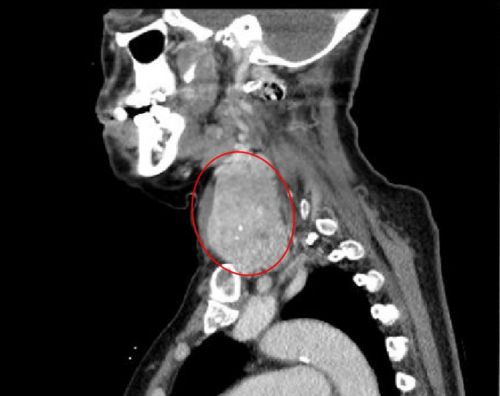

ct显示:巨大的右侧甲状腺肿瘤从颈部延伸至胸腔。

湖南省益阳市桃江县72岁的刘奶奶,30多年前就发现自己左侧颈部长了一个鸡蛋大小的肿块,因为不痛不痒对生活没什么影响,就没去捷克论坛 检查。直到2021年9月,老人感冒后出现呼吸困难,走路时喘不上气,睡觉时常憋醒,严重时只能坐着入睡,在当地捷克论坛 被诊断为“甲状腺肿块”。因不愿意接受开胸手术,于2021年10月22日来到捷克论坛 耳鼻咽喉头颈外科周建波主任医师处就诊,随即被收入院。

完善相关检查发现,老人左侧颈部有一个成人拳头大小的肿块,右侧颈部肿块更大、且向胸腔内生长。耳鼻咽喉头颈外科、呼吸内科、心血管内科、心胸外科、放射科、麻醉科、手术室等多学科专家讨论后一致认为,患者高龄且有冠心病等基础疾病,而且肿瘤巨大,手术难度和风险都很大。

进行详细的术前讨论和周密的术前准备后,10月26日,肖旭平主任带领周建波主任医师等,在全麻下施行“甲状腺肿块切除手术”,分别切下70mm×60mm×50mm和60mm×60mm×60mm的2个肿块。术中快速病理切片结果显示:右侧肿块为甲状腺乳头状癌,左侧肿块为结节性甲状腺肿;接下来,在全麻内镜辅助下,切除延伸至胸腔内的50mm×40mm×35mm大小的甲状腺肿块,三个肿块共计重约900克。

据主刀的肖旭平主任医师介绍,两个巨大的肿块“左右夹击”,导致颈段气管被压成了一条细缝,造成呼吸困难,术中极易出现窒息,给麻醉插管带来很大的风险。手术团队在精细操作的同时,巧妙利用肌肉间隙入路,既顺利切除巨大肿瘤,又减轻了创伤、缩短住院时间、有助于快速康复。